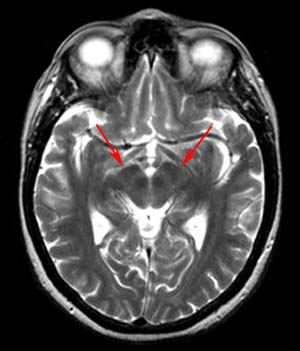

Radiographically Parkinson's disease appears as nonspecific atrophy with enlarged lateral ventricles and widened sulci on CT. On MR, decreased width of the pars compacta between the pars reticularis and the red nucleus may be evident. Otherwise, no statistically significant differences in signal intensity or size of the pars compacta have been substantiated.

![]() ![]() The two images above are T2-weighted axial images through the midbrain. |